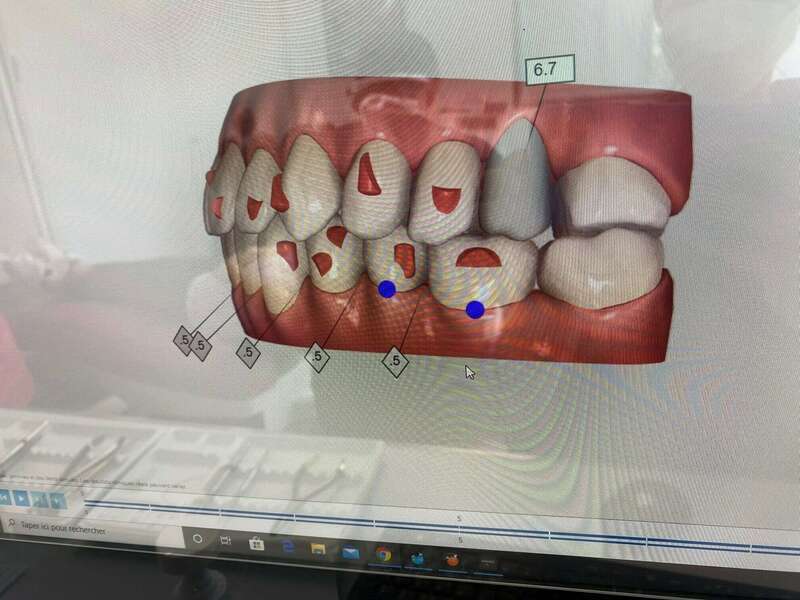

Des technologies au service de la précision

Empreinte optique

Dites adieu aux empreintes classiques ! Cette technologie numérique capture une image en 3D de vos dents pour une précision accrue et un confort optimal.